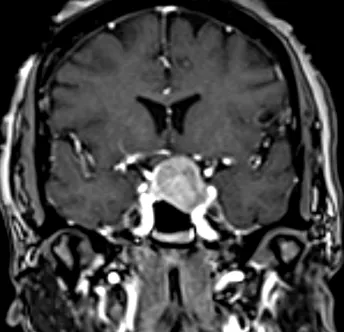

Pre- and Post-Op Pituitary Macroadenoma

Post-Op Pituitary Tumor Surgery Image 2

Post-Op Pituitary Tumor Surgery Image